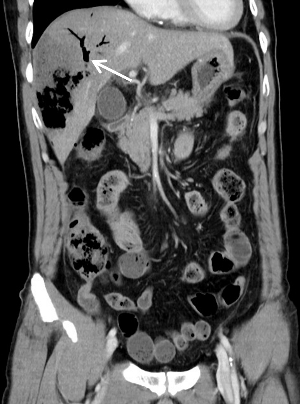

1 病例资料患者,男性,61岁,1 d前(2020-10-9 10点左右)因“无明显诱因出现持续性腹痛”,至外院急诊就诊,腹部CT提示无明显急诊征象(图 1)。实验室检查:白细胞7.25×109/L,中性粒细胞比率75.5%,淋巴细胞比率19.3%,生化提示天门冬氨酸氨基转移酶108 U/L,淀粉酶103 U/L,肌酐73 µmol/L,C-反应蛋白2.4 mg/L,给予解痉、消炎、止痛等对症治疗后出现呕吐、畏寒发热,体温最高超39℃,降温后回家,仍有腹痛、呼吸急促,自行服用三九胃泰。

| 图 1 患者全腹部CT平扫未见明显急诊征象 |